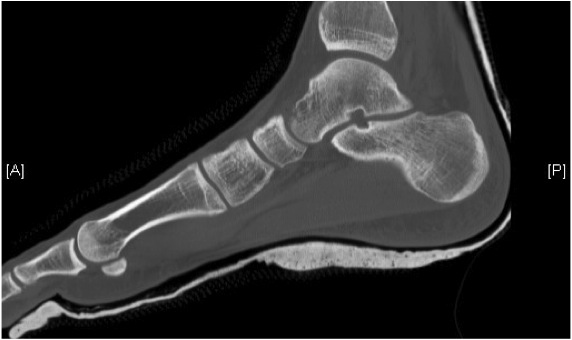

Medial subtalar dislocation

1. Medial

- calcaneum dislocated medially

- more common

- forced inversion in plantar flexed position